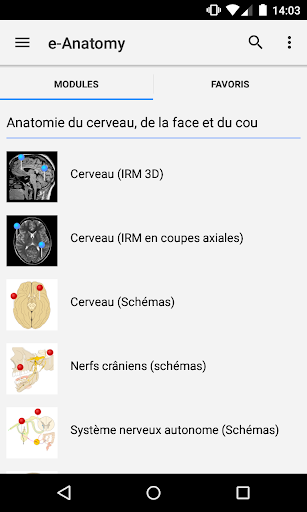

New : You can now filter the modules by region or by content type so you can find the module you are looking for much faster.

-Two new modules : Brain - TOF and Brain Angiography, Atlas of normal neurovascular anatomy of arteries of the brain on a cerebral angiogaphy.-The interface has been reworked.-A new tab named "QuickLinks" is available, dispatching modules in sections of the human body and allowing you to fast travel to the modules you are looking for.-Fixed small bugs.